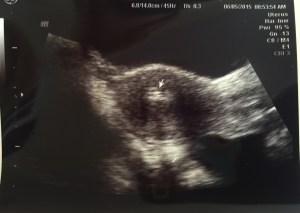

Please continue to keep my ever growing little family in your prayers. I go back to the doctor Thursday for repeat blood work to make sure my numbers are doubling every few days, a blood flow ultrasound to make sure my arteries are pumping an adequate blood supply to my uterus and an ultrasound to hopefully see if we have one little Pipplet in there or 2.